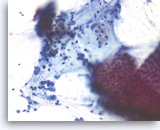

Non-Hodgkin B-cell lymphoma,

Pancreas FNA, Cell Block.

Atypical lymphoid infiltrates are present in fibrotic tissue fragment. The atypical cells are intermediate to large in size and have irregular nuclear contours and conspicuous nucleoli. Flow cytometry of the aspirates demonstrates a monoclonal B-cell lymphoma. Overall, the findings are consistent with diffuse large B-cell lymphoma.

40X

Non-Hodgkin B-cell lymphoma,

Pancreas FNA, Cell Block.

Atypical lymphoid infiltrates are present in fibrotic tissue fragment. The atypical cells are intermediate to large in size and have irregular nuclear contours and conspicuous nucleoli. Flow cytometry of the aspirates demonstrates a monoclonal B-cell lymphoma. Overall, the findings are consistent with diffuse large B-cell lymphoma.

40X